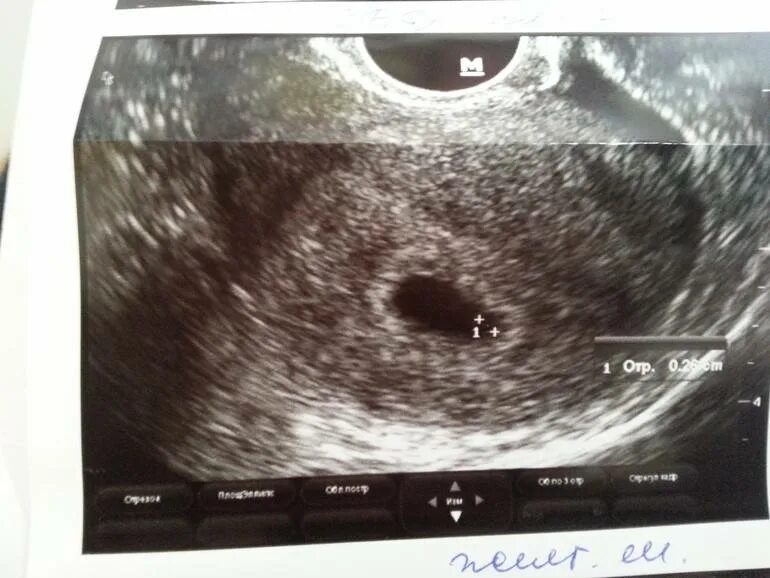

Не видно эмбриона на 6 неделе беременности